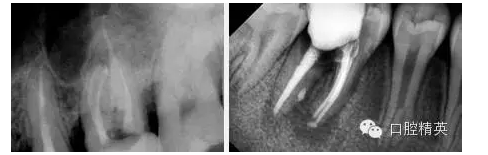

在預(yù)備一顆牙齒或使用任何根管擴(kuò)大針之前,必須要進(jìn)行全面的操作評(píng)估。根據(jù)初次或再次治療的預(yù)期治療,可以評(píng)估操作的難度及可能出現(xiàn)的失誤。這樣我們就可以成功防止發(fā)生問(wèn)題。根管治療最忌留有殘髓,理論上擴(kuò)管至根尖0.5-1.0mm,實(shí)際上治療操作根管測(cè)量只宜作參考數(shù)字,口腔精英微信號(hào)KQJY--2000

,醫(yī)生的手感經(jīng)驗(yàn)最重要。教科書(shū)上介紹當(dāng)根管近根尖時(shí)操作可以有較明顯的阻力感,實(shí)踐中我認(rèn)為按序逐步后退深入法擴(kuò)管應(yīng)該是最科學(xué)的操作,無(wú)論如何不易將根管感染物推至根尖外。該法是大致是先從小號(hào)K銼旋入根管近三分之一時(shí)順時(shí)針旋轉(zhuǎn)一到二圈后退,再以H銼同法磨銼管壁去除腐物,根管沖洗液沖洗,逐號(hào)擴(kuò)管逐步深入至根尖孔。在接近根尖孔時(shí)可以用比最小號(hào)H銼大二號(hào)的H銼試探一下阻力,并可以防止根管銼將根管感染物推至根尖外。前牙及前磨牙基本上可旋至最大號(hào)根管銼到根尖,磨牙則變化較大,手感為主要參考,不宜強(qiáng)行擴(kuò)管,以免斷針。H銼在去除管壁腐物的作用尤其重要。鎳鈦機(jī)用根管擴(kuò)大針畢竟代價(jià)太高,一般使用不多。它的使用一方面可以大大減輕醫(yī)生的工作強(qiáng)度,對(duì)彎曲根管的制備也有較好的效果。沖洗液后牙一般300ml左右(我將在以后的文章中專門介紹鎳鈦機(jī)用根管擴(kuò)大針)??傊茴A(yù)備是一個(gè)需要一定經(jīng)驗(yàn)總結(jié)的過(guò)程。

新的研究上認(rèn)為上頜第一、二磨牙近頰根管變異大,近頰可以有1-3個(gè)根尖孔,近頰根主根管(MB1)位于根尖頂者近一半,MB2位于根尖頂者上頜第一磨牙約為7%,上頜第二磨牙約為26%,各型根尖孔多位于根尖遠(yuǎn)中或舌側(cè)。MB2根尖孔到解剖根尖約1.5-2.5mm第一磨牙平均2.03mm,第二磨牙平均1.82mm,MB2在工作實(shí)踐中在確定根管工作長(zhǎng)度時(shí)不能常規(guī)的以距根尖孔0.5-1.0mm作為測(cè)量標(biāo)準(zhǔn)。

多數(shù)MB1、MB2的根尖1/3彎向遠(yuǎn)中,MB2在近根管口1-3mm處明顯彎向近中,,根管中段較直,研究顯示MB2在離體上頜第一磨牙的出現(xiàn)率近90%,臨床上通過(guò)將上頜第一、二磨牙開(kāi)髓口改良為斜四邊形及去除髓腔近中壁牙本質(zhì)懸突可提高M(jìn)B2的出現(xiàn)率。